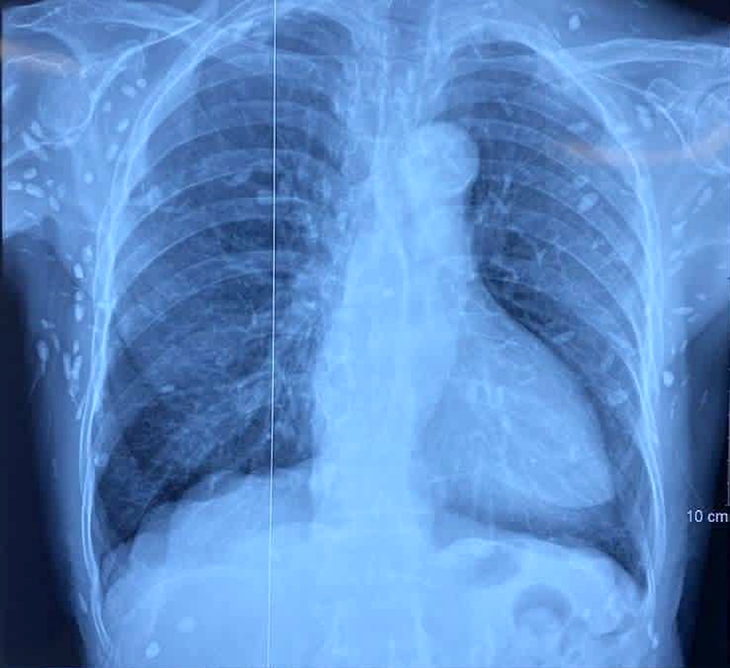

Người bệnh được chẩn đoán nhiễm ấu trùng sán dây lợn. Hình ảnh cắt lớp vi tính sọ não và X-quang ngực cho thấy rất nhiều nốt cản quang trong nhu mô não và dưới da vùng ngực - bụng.

Nhiều nốt cản quang dưới da thành ngực - bụng và chi trên - Ảnh: BVCC